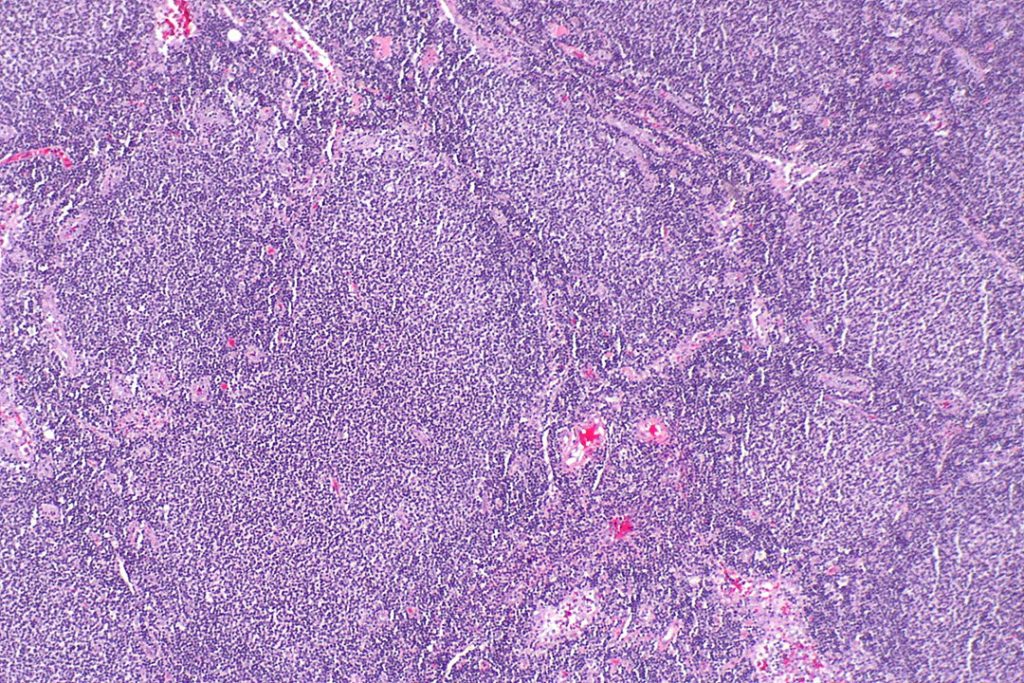

Фолликулярная лимфома (ФЛ) является наиболее распространенной индолентной (медленно развивающейся) формой неходжкинской лимфомы (НХЛ), на которую приходится примерно каждый пятый случай НХЛ. Она довольно хорошо поддается лечению, но характеризуется периодами ремиссии и рецидивами. Лечение заболевания становится сложнее с каждым новым рецидивом, а раннее прогрессирование может характеризовать неблагоприятный прогноз. По оценкам, в 2022 г. в Соединенных Штатах будет диагностировано около 13 000 новых случаев ФЛ, и ежегодно во всем мире ФЛ диагностируется более чем у 100 000 человек[iv],[v].

Мосунетузумаб представляет собой биспецифическое анти-CD20xCD3 антитело, разработанное для направленного воздействия на CD20 на поверхности В-клеток и CD3 на поверхности Т-клеток. Это двойное направленное воздействие активирует и перенаправляет существующие Т-клетки пациента для уничтожения опухолевых В-клеток с помощью цитотоксических белков, высвобождаемых внутрь В-клеток. В настоящее время проводится полноценная программа клинических исследований мосунетузумаба, изучающая молекулу в монотерапии и в комбинации с другими лекарственными препаратами для лечения пациентов с неходжкинскими лимфомами, включая фолликулярную лимфому и диффузную В-крупноклеточную лимфому, а также другие виды гематологических заболеваний.